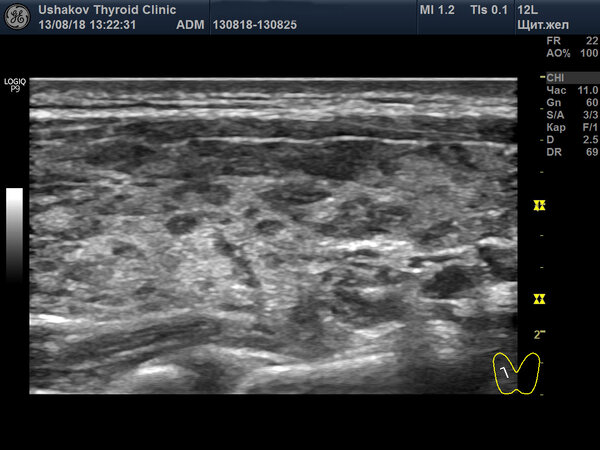

Предлагаем сравнить ультразвуковые снимки одной и той же пациентки (личные данные удалены, сохранены даты исследований). Обратите внимание на гипоэхогенные (тёмные) участки в правой доле щитовидной железы на снимке от 13 августа 2018 года.

Эти тёмные зоны соответствуют участкам, где собственная ткань железы была значительно разрушена и замещена скоплениями иммунных клеток (лимфоцитов). Важно отметить, что активность лимфоцитов не всегда носит исключительно разрушительный характер; они также участвуют в очистке ткани и создании условий для потенциальной регенерации, которая возможна при благоприятных обстоятельствах.